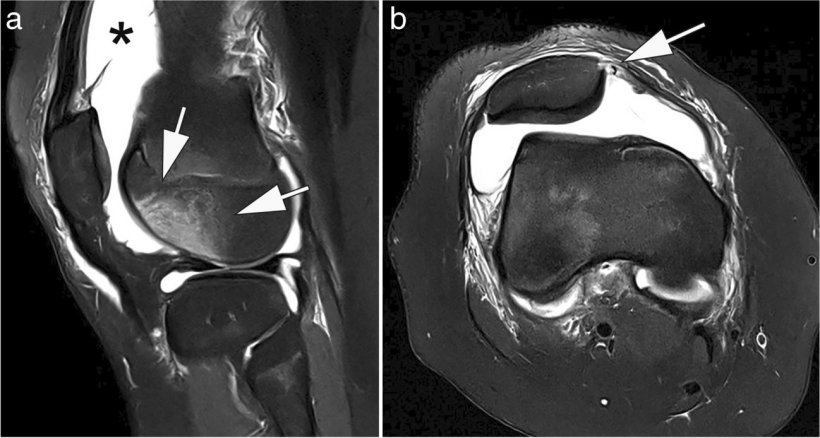

Image source: Pogarell T, Heiss R, Janka R, Nagel AM, Uder M, Roemer FW, Skeletal Radiology 2024 (CC BY 4.0)

Vilanova, who will chair the ESMRMB 2026 meeting, has made low-field implementation a cornerstone of his clinical strategy. In Marseille, he laid out a detailed case for its integration into routine practice: economic sustainability, sufficient diagnostic quality for MSK and spine imaging, and growing support from AI technologies.

‘In my clinic, nearly 80% of MRI requests are for spine or MSK,’ he explained. ‘The question is not whether we can produce beautiful images – the question is whether we can answer the clinical question.’

For knee pain, lumbar discomfort or degenerative joint changes, low-field MRI offers enough diagnostic clarity at a fraction of the cost of high-field scans. ‘We’re not talking about advanced cardiac or prostate imaging,’ he added. ‘We’re talking about the everyday core of radiology, where efficiency matters most.’